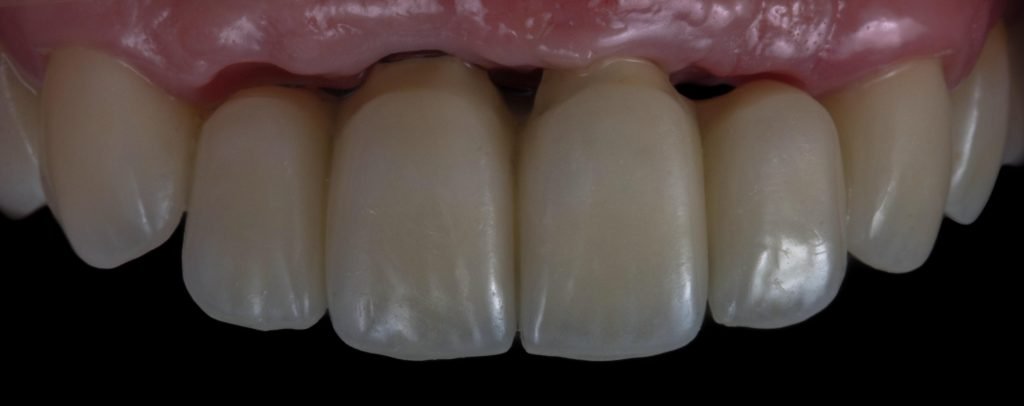

Punto Bajío Casos Clínicos Prótesis Fija sobre Implante unitario Inicio Provisional Final Prótesis Parcial Fija sobre 2 Implantes 2 Implantes Final Prótesis Bucal Removible Inicial Inicial Superior Inicial Inferior Rayos X Inicial Rayos X Inicial Frontal Final Final Superior Final Inferior Prótesis Parcial Fija/ Coronas de Circonio Sonrisa Inicial Foto Inicial Foto Inicial Inferior Foto Final Inferior Foto Final Sonrisa Final Prótesis Total Protesis Inmediatas 1 Protesis Inmediatas 2 Prótesis Removible/ Coronas Metal-Ceramica Carillas Incrustaciones Endodoncia